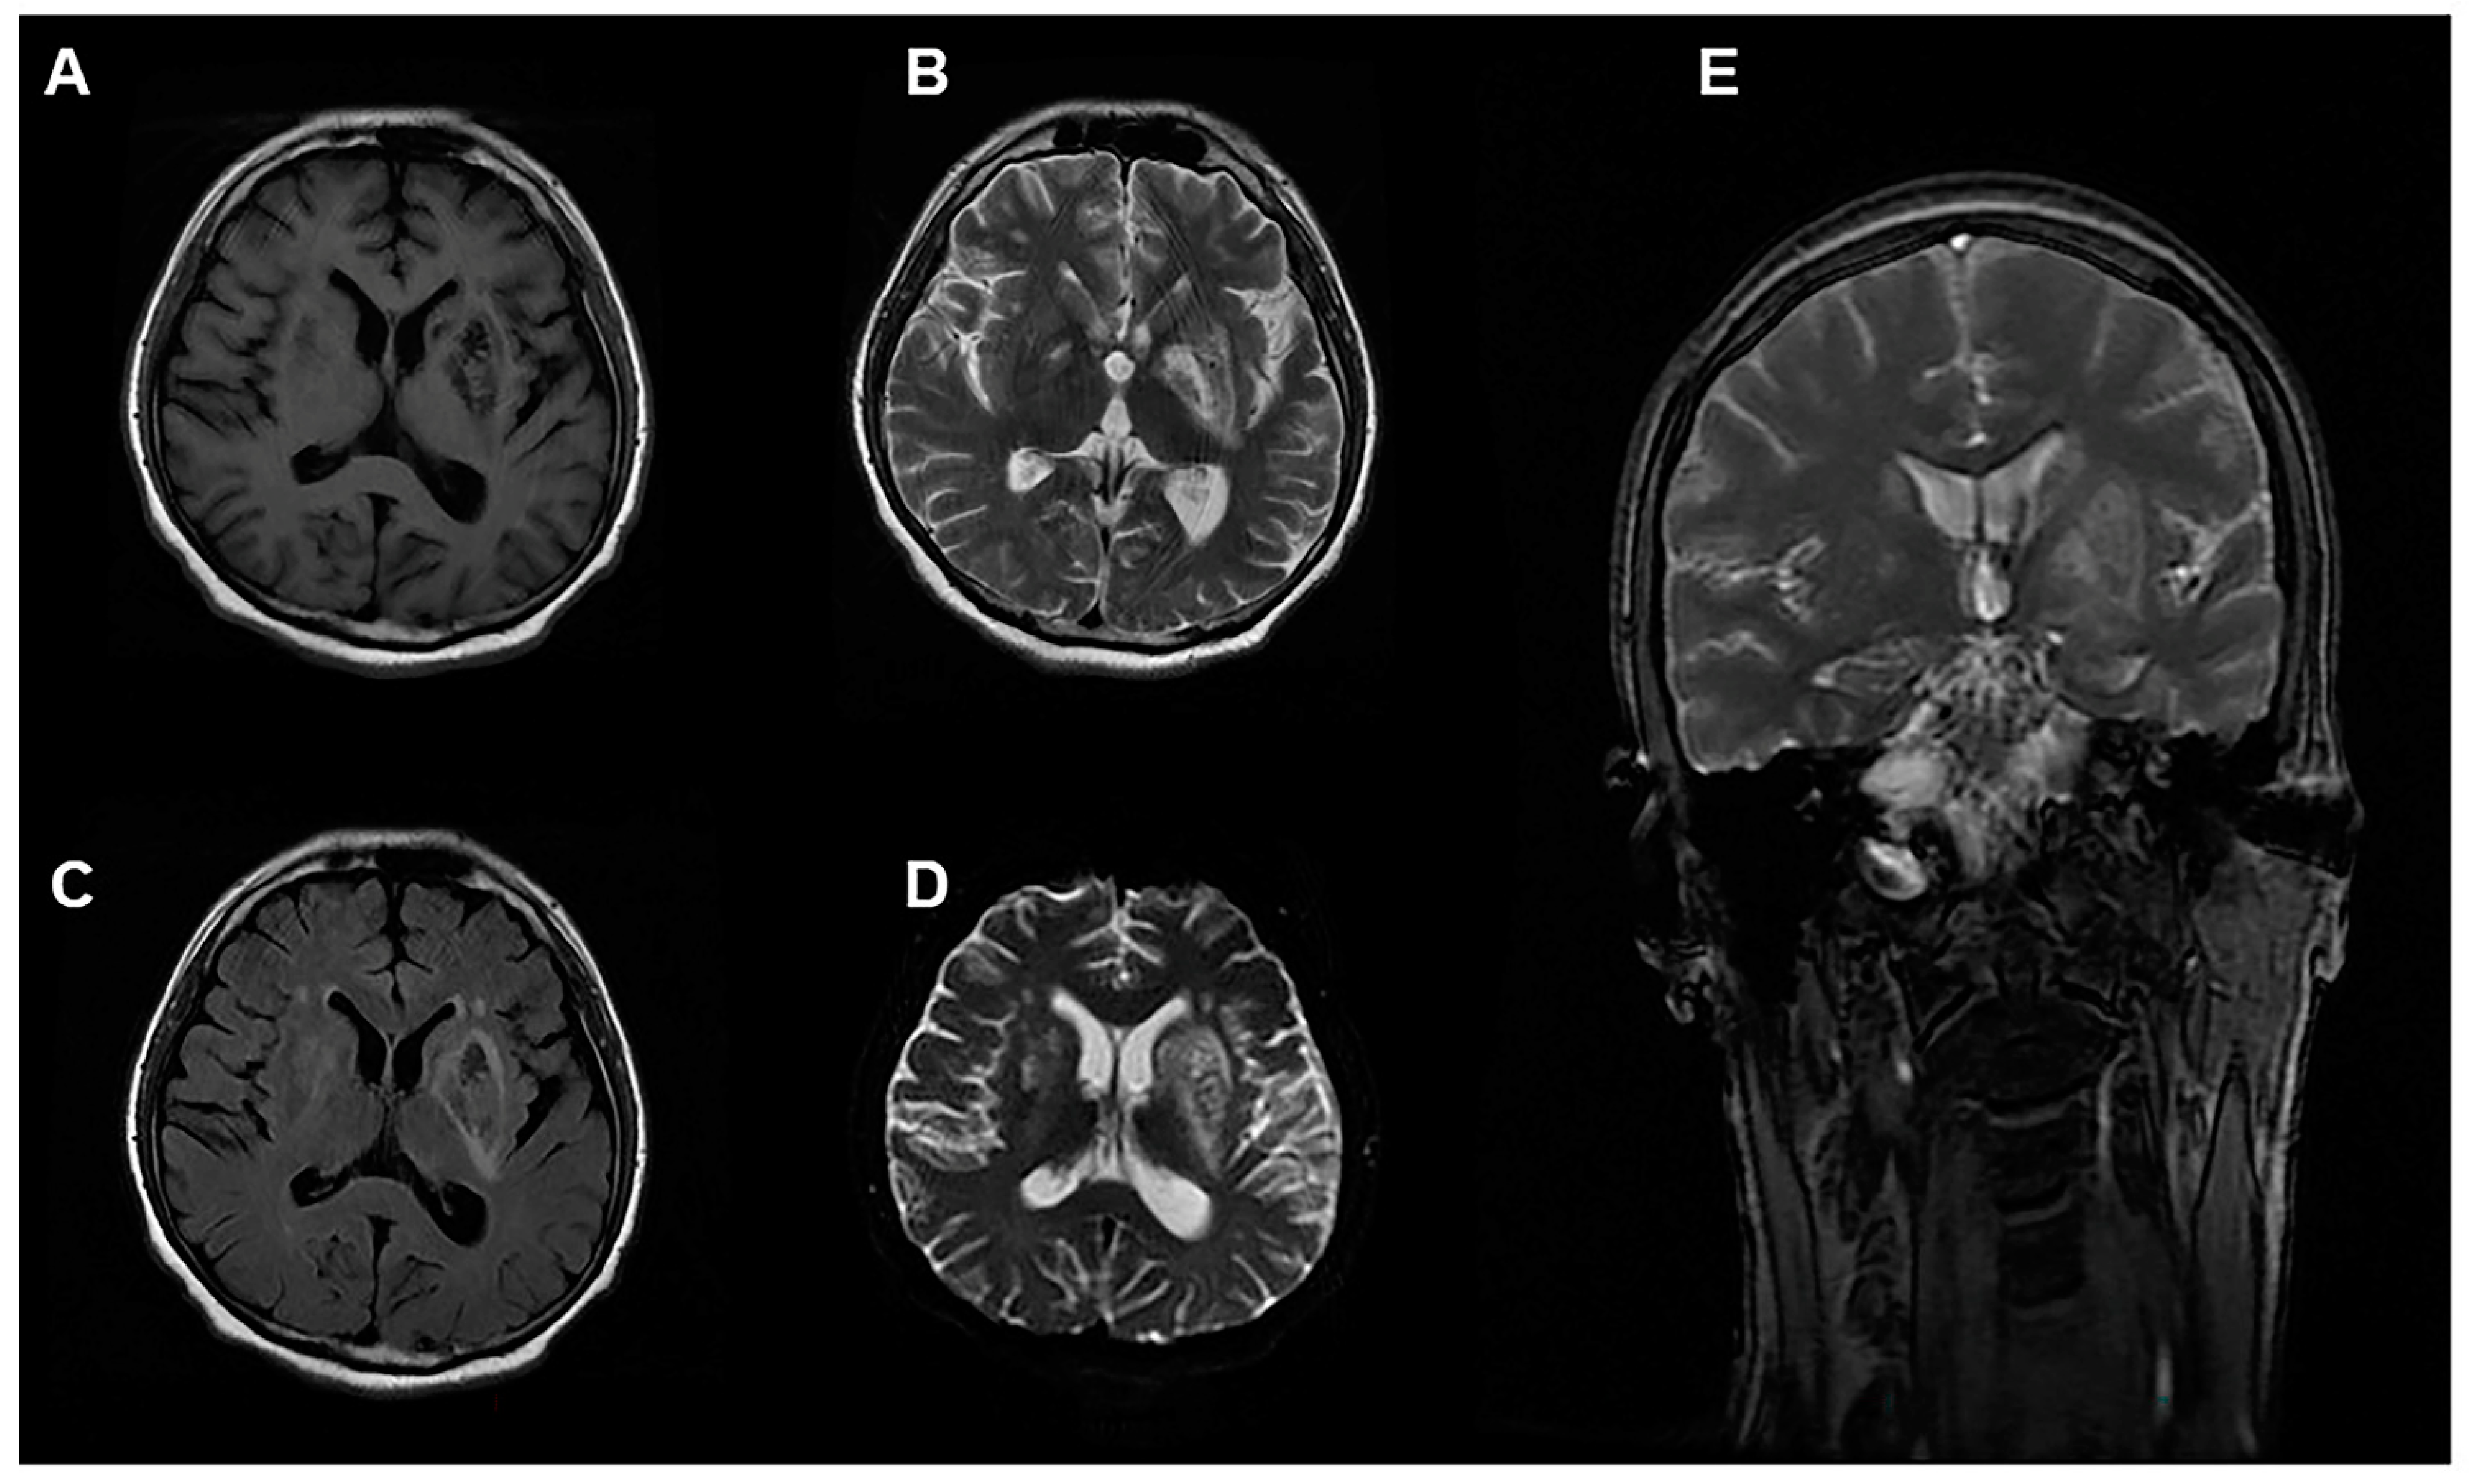

2. Case Presentation